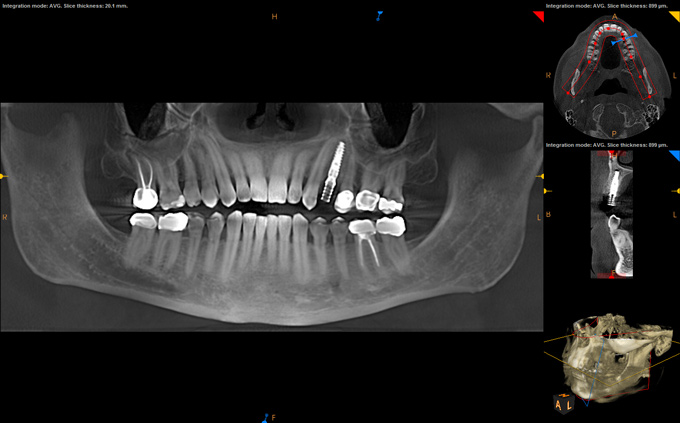

After a CBCT scan (Figure 3) and a digital impression were obtained for diagnosis and treatment planning, the DICOM file from the CBCT scan and the STL file from the digital impression were merged in a treatment planning software application for evaluation. A virtual crown was then created to facilitate a restoration-driven approach. The vital structures and osseous anatomy were identified, and the implant position was planned virtually (Figure 4 and Figure 5).

(4.) Digital plan of the virtual implant.

Figure 4

(5.) Digital plan of the virtual implant.

Figure 5